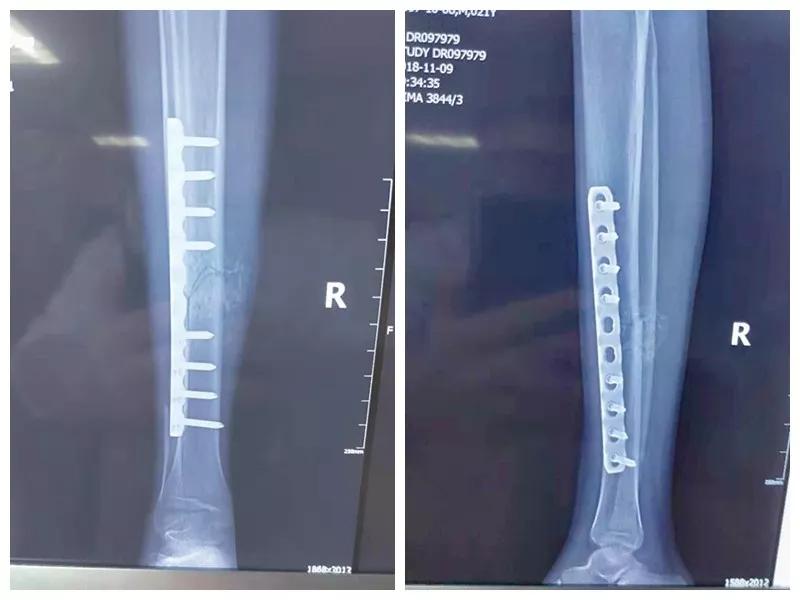

骨二科张延平主任接诊后经仔细询问病史,详细阅读近期X线、CT等病历资料,认为患者骨折移位明显,目前骨折无任何愈合迹象,若保守治疗,骨折将无法愈合,后期不能下地活动,严重影响患者生活质量。同时患者合并慢性再障,血常规结果各项指标均极低,围术期发生麻醉意外、大出血、感染等风险极高;而我院作为西安市级最大的三甲综合21点游戏规则 ,综合实力深厚,既往相关疾病治疗经验丰富,多次通过多学科诊治为合并复杂内科疾病患者保驾护航,为患者创造手术时机,提高患者生活质量,遂将患者收住院。住院后,立即成立了由张延平主任、杨寅副主任、山卉护士长、梁晨主治医师、刘邦定主治医师、李鑫护师组成的手术治疗小组。经初步检查,患者血常规结果较当地检验结果更差,三系细胞均极低,其中血小板仅为1(正常值为100-300),血红蛋白55g/L。遂立即请血研所李罡灿主任医师会诊,给予升高白细胞、纠正贫血、升高血小板等治疗,经积极治疗患者血常规各项指标均较入院时改善。张延平主任再次组织由血研所李罡灿主任医师、麻醉科崔晓岗主任、感染科付建军主任、药剂科韩小年副主任药师等参加的术前讨论。讨论后一致认为患者目前各项指标虽然较入院时改善,但因其慢性再障病史长,骨髓造血及储备能力极差,围术期发生大出血、伤口感染甚至全身感染等风险仍极高,术中及术后需准备大量血小板防止大出血,同时需高度警惕手术切口、取骨区术后发生感染。为尽快为患者施行手术,治疗小组积极联系输血科为患者备血,并为患者制定了围术期抗感染方案;在我院输血科存血量严重不足的状态时,输血科张养民主任亲自联系市中心血站为患者准备手术中及术后所需的血小板制品。手术小组为患者制定了周密的手术方案及风险预案,10月31日,在麻醉科王永宏副主任医师、手术室高洁、赵耀护师的配合下,为患者施行了右胫骨粉碎性骨折切开复位、髂骨取骨植骨内固定术,手术历时70分钟,安全返回病房。术后患者渗血多,1周内连续每日平均渗血超过100ml,并出现发烧,最高39℃,复查血常规三系细胞较术前再次明显降低。李罡灿主任医师、付建军主任、韩小年副主任药师多次来科会诊,及时调整患者的治疗方案,输血科再次为患者的救治提供了强有力的支援和保障。在山卉护士长带领的护理团队精心护理下,患者未发生压疮等卧床并发症。目前该患者术后恢复良好,已出院进行下一步康复治疗。